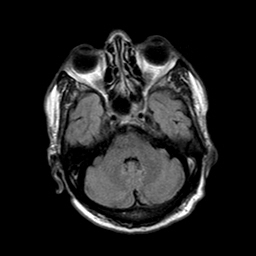

Radiological images: